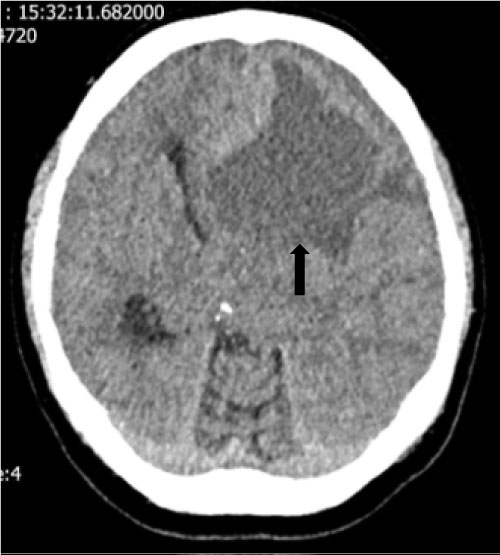

A non-enhanced computed tomography (NECT) of the head (Figure 1) showed large hypodense mass (5 × 6 cm) in the left frontal lobe with hyperdense margin crossing midline and compressing the frontal horn of left lateral ventricle. Our differential diagnosis centred around glial based tumour with very little possibility of an abscess based on imaging features.

Figure 1: Shows hypodense lesion (black arrow) compressing the left frontal horn. View Figure 1